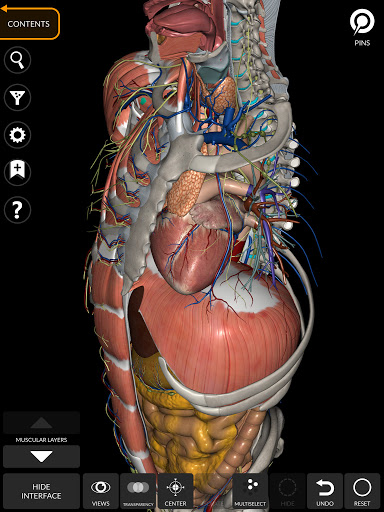

"Anatomy 3D Atlas" vous permet d'étudier l'anatomie humaine de manière simple et interactive.

Grâce à une interface simple et intuitive, il est possible d'observer chaque structure anatomique sous n'importe quel angle.

Les modèles anatomiques 3D sont particulièrement détaillés et avec des textures jusqu'à une résolution de 4k.

La subdivision par régions et les vues prédéfinies facilitent l'observation et l'étude de parties individuelles ou de groupes de systèmes et les relations entre différents organes.

MODÈLES ANATOMIQUES 3D

• Système musculo-squelettique

• Système cardiovasculaire

• Système nerveux

• Système respiratoire

• Système digestif

• Système urogénital (homme et femme)

• Système endocrinien

• Système lymphatique

• Système oculaire et auditif

• Visualisation des muscles à travers des niveaux de couches depuis les plus superficielles jusqu'aux plus profondes